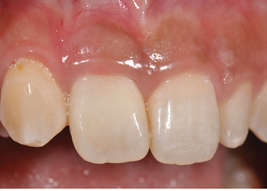

(17.) Postoperative view 1 month after provisional restoration.

Figure 17